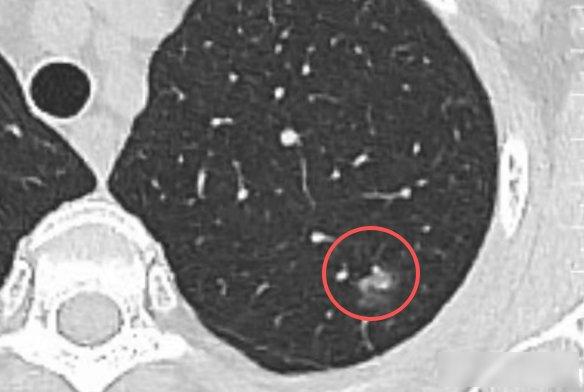

说一个很多人不知道的真相:现在很多人做胸部CT检查,几乎都会查出肺结节。

我上周陪表姐做CT,她盯着报告上那三个字,肺结节,手一直在抖,这种事我见得多了,医院放射科每天都有人攥着片子问,医生这东西会变癌吗,要多久,其实很多检查结果,根本没那么严重。

肺结节就像蚊子叮完皮肤留下的小包,多数是身体自己好起来的痕迹,你吸的每一口空气里都有灰尘、花粉、细小的细菌,它们进了肺,免疫系统就动手清理,清理完留下一点小疤,CT一照就成了白点,跟皮肤伤口结痂后变的色印一样,这些小疤不会要命。

真正要小心的恶性结节,跟中彩票差不多少,从细胞开始异常,到长成肿瘤,一般得五到七年,就像地里埋下的种子,前两年顶多冒点嫩芽,再过几年才长成小树苗,这时候发现,做个微创手术,就能把根除掉,我去年接诊一个病人,肺里有个零点八厘米的结节,已经有点不对劲,做完手术,五年复查,一切都没问题。